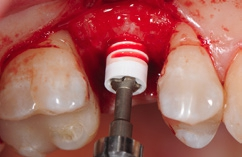

Die Implantate wurden im Anschluss mit einer ausreichenden Primärstabilität von 30 Ncm und einem suprakrestalen Anteil 0,6 mm platziert. Diese suprakrestale Positionierung wird durch einen gegebenenfalls am Profilbohrer anbringbaren Tiefenstopp (Abb. 7) vereinfacht. Für das Einbringen der Implantate steht ein neues, zur „Inter-X“-Innenverbindung formschlüssiges Eindrehinstrument (Abb. 8) zu Verfügung, wodurch eine optimale Kraftübertragung während des Inserierens des Implantats gewährleistet wird (Abb. 9). Die Einheilkappen sind deutlich abgeflacht und ermöglichen einen einfachen primären Wundverschluss (Abb. 10 und 11). Im vorliegenden Fall verlief die Wundheilung komplikationslos. Nach einer auch für Keramikimplantate heute üblichen Einheilungszeit von 3 Monaten zeigten sich die Implantate in der Röntgenkontrollaufnahme stabil osseointegriert (Abb. 12). Es fanden sich an beiden Implantat-Loci entzündungsfreie Weichgewebsverhältnisse, woraufhin mit der prothetischen Versorgung des Implantats begonnen werden konnte.

Für den Reentry wurde für das Einbringen des Gingivaformers eine minimale krestale Inzision angelegt (Abb. 13). Nach Abheilung der Weichgewebe (Abb. 14) konnte 2 Wochen später mit Reposition des Abformpfostens geschlossen abgeformt (Abb. 15) und das Meistermodel erstellt werden Da es sich um ein 2-teiliges Implantatsystem handelt und die Abutments ebenfalls aus hochfester ATZ-Keramik bestehen, lassen sich diese – falls nötig – entweder in der Praxis oder im Dentallabor durch Beschleifen individualisieren (Abb. 16). Für NobelPearl stehen sowohl gerade als auch 15° abgewinkelte Abutments mit 1 mm und 3 mm Gingivahöhe zu Verfügung. Im CAD/CAMVerfahren wurde eine monolithische Zirkonkrone aus Zolid FX (Amman Girrbach) mit okklusalem Zugang zum Schraubenkanal gefertigt (Dentallabor Studio für Zahntechnik, Dirk Tartsch).